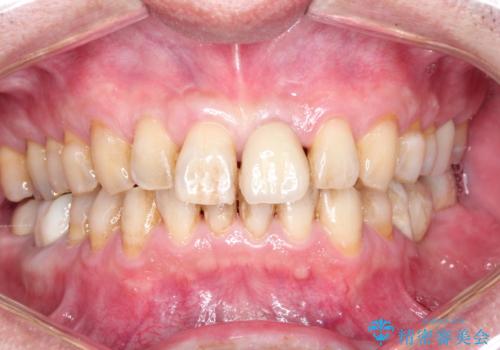

ステインによる歯の着色

治療症例の内容

- 50代男性

- 1日

- 1回

- 日頃の積み重なった茶渋・着色をエアフローにてクリーニングしました。

- 12000円+TAX (PMTC“エアフロー”60分コース)費用は治療当時の料金となります

歯についている茶しぶやタバコによるヤニは着色を落とす専用器具を使用しないと綺麗に取り除くことはできません。

歯の表面に着色が付いて黄ばんで見えることがあるため、PMTCを行うとご自身の歯本来の色味にすることができます。